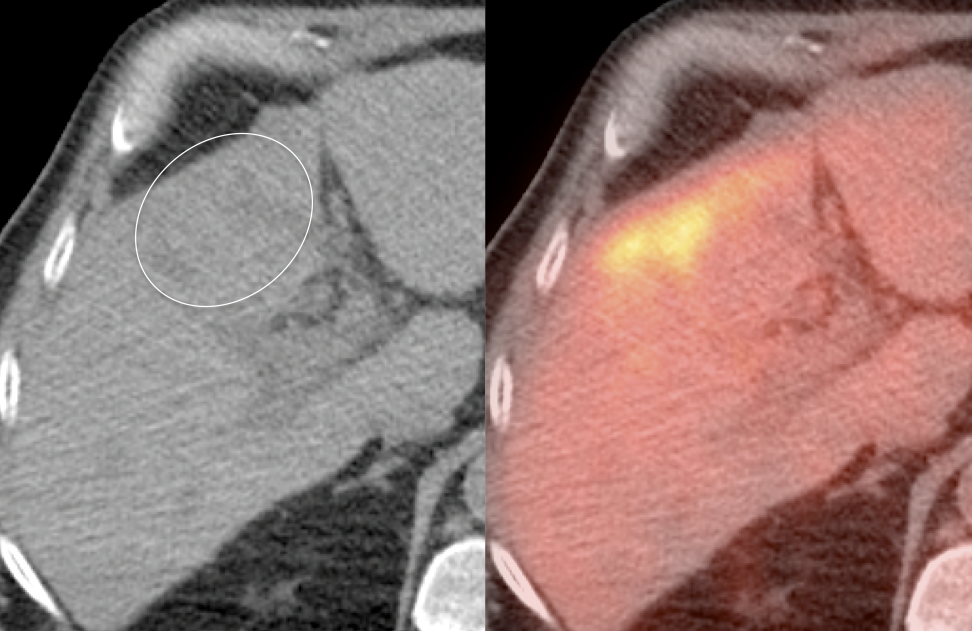

Diffuse intense gallbladder uptake associated with wall thickening, pericholecystic fluid or gallstones is suspicious for cholecystitis. In such cases, ultrasound correlation is strongly recommended, “Ultrasound correlation is recommended in this case to exclude acute cholecystitis.”

While focal intense gallbladder wall uptake can be seen with benign polyps, adenomyomatosis or focal inflammation associated with cholecystitis, malignancy must be excluded.

False Positives:

- Normal Physiologic Uptake

- Polyps & Adenomyomatosis

- Cholcystitis, Acute or Chronic